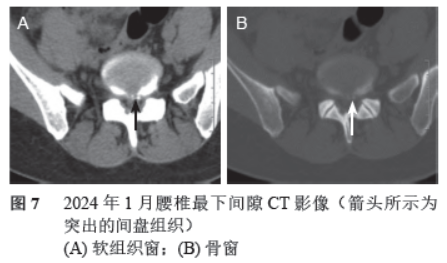

期间于2023年2 月病人再次出现左下肢麻木后行1 个疗程椎旁神经阻滞治疗,症状缓解后持续至今。2024 年1 月随访后复诊,主诉久坐及劳累后仅左下肢可出现轻微不适,休息后即可缓解,复查腰椎CT 可见突出物钙化点(见图7),表明突出物渐趋稳定。